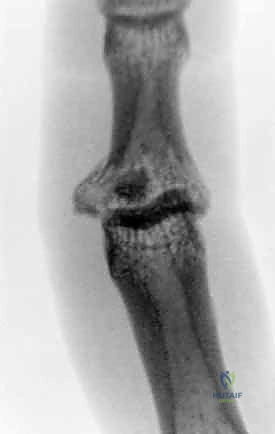

2. التصوير بالأشعة السينية (X-Rays)

هو المعيار الذهبي الأولي. يجب أخذ صور شعاعية واضحة ومحددة للإصبع المصاب (وليس لليد بأكملها) في ثلاث وضعيات:

* الوضعية الأمامية الخلفية (AP): لتقييم المحور الجانبي للإصبع والبحث عن شقوق عظمية.

* الوضعية الجانبية الحقيقية (True Lateral): هي الصورة الأهم على الإطلاق. من خلالها يتم تحديد حجم القطعة العظمية المكسورة، ومقدار انزياح المفصل. يبحث الجراح الماهر هنا عن علامة "V-Sign" الشهيرة، والتي تدل على عدم تطابق الأسطح المفصلية ووجود خلع جزئي غير مستقر.

* الوضعية المائلة (Oblique): تساعد في رؤية تفاصيل الكسور المفتتة التي قد تختفي في الوضعيات الأخرى.